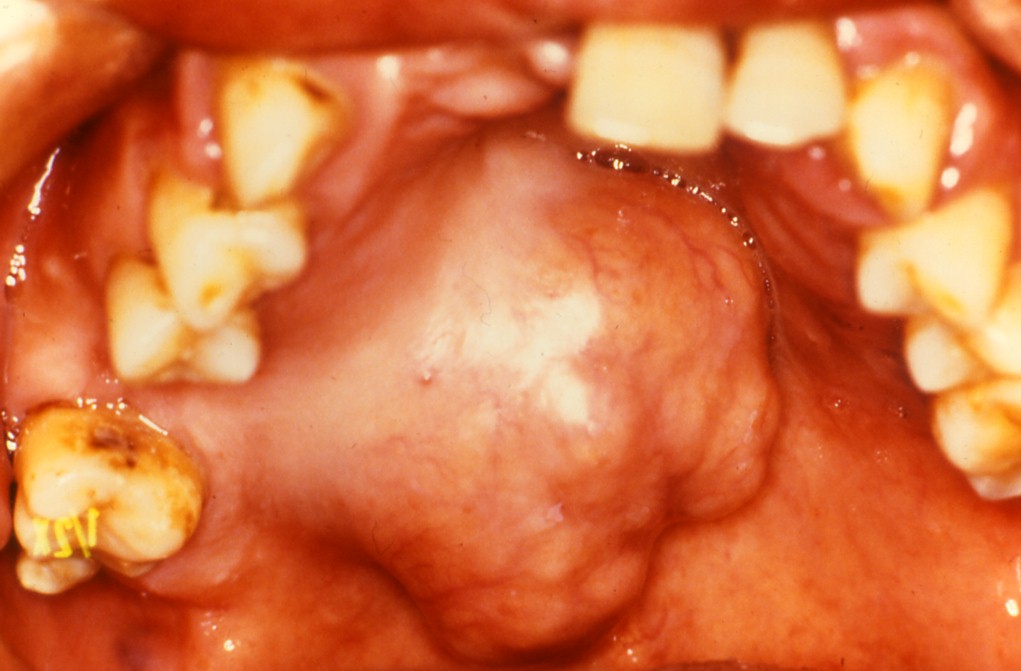

45歳男性 エナメル上皮腫

28歳女性 エナメル上皮腫